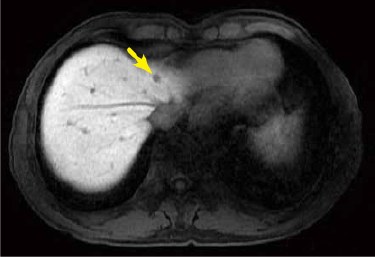

Fig. 2. EOB-MRI images

The metastases in S4 and S5 of the hepatic right lobe detected with PET-CT were also detected in the hepatobiliary phase of EOB-MRI, and the nodule in S5 showed ring-shaped contrast enhancement in the arterial phase. In addition, a new small nodule, no more than 5 mm in diameter, and showing reduced EOB uptake, was found in the dorsal region.

Hepatobiliary phase

Arterial phase